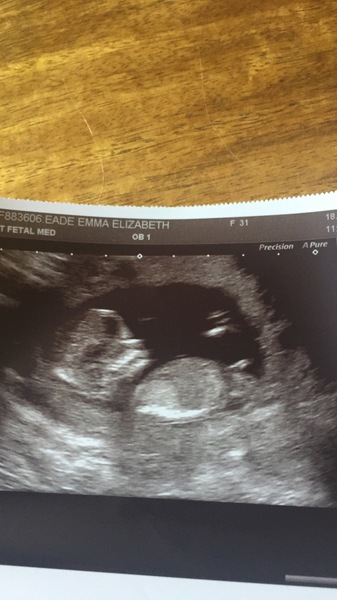

Just to update myself, I'm 31 pg with baby no.3 (dd7 and ds4) and edd 16th Feb! Got my 12 week scan 2 weeks on Friday and a little nervous/excited !!